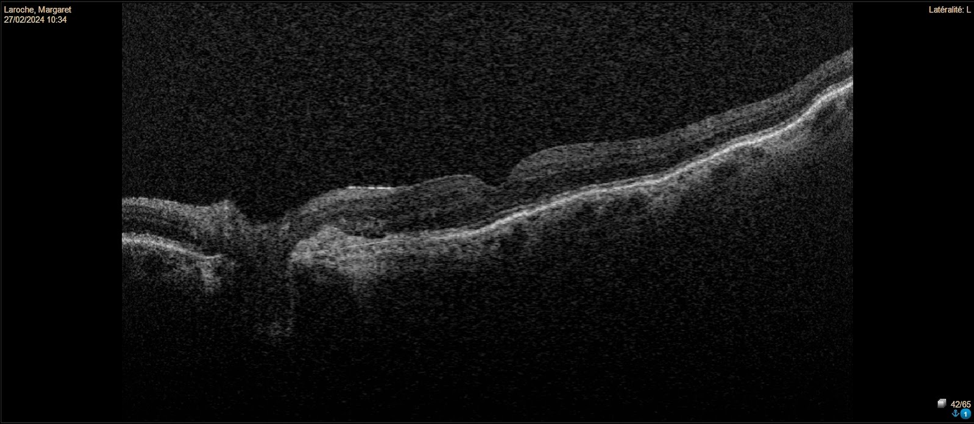

This patient has peripapillary choroidal neovascularization (CNV) in the left eye. Fundus photos reveal drusen and pigmentary changes consistent with dry AMD in the right eye. The left eye shows peripapillary atrophy suggesting a chronic process. OCT imaging of the right eye shows drusenoid pigment epithelial detachments (PEDs), while the left eye has a fibrous PED with overlying subretinal fluid extending close to the parafoveal area. Peripapillary CNV can fluctuate over time but is usually self-limited without foveal involvement. Observation is recommended, along with advising the patient to monitor vision with an Amsler grid.

Peripapillary choroidal neovascularization in AMD tends to have a more benign course than classic CNV, with less frequent involvement of the fovea and slower progression.